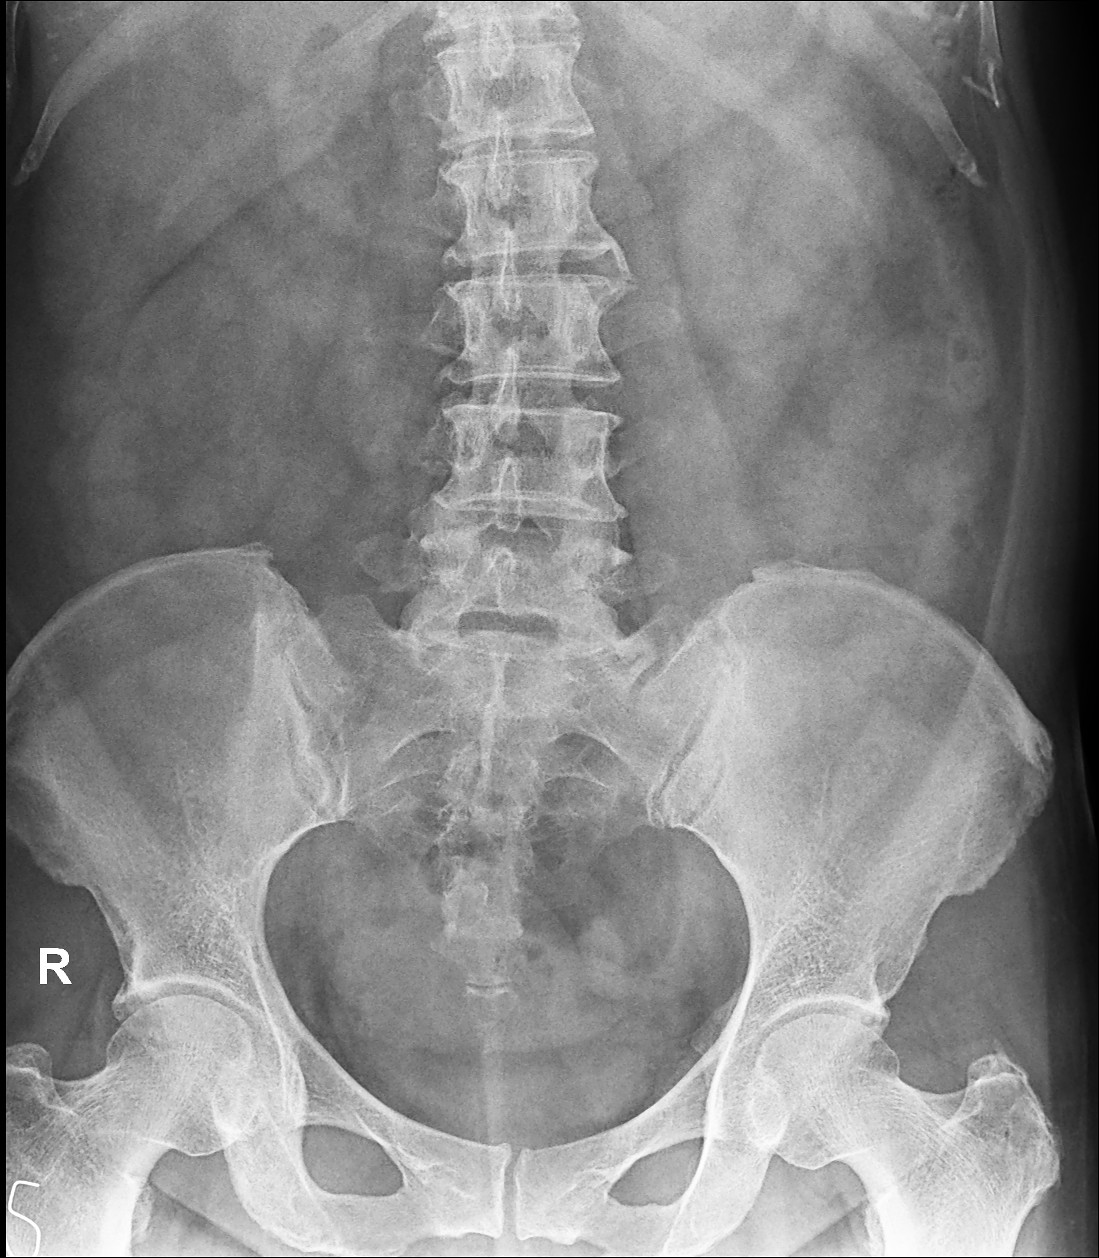

Mild lumbar levoscoliosis